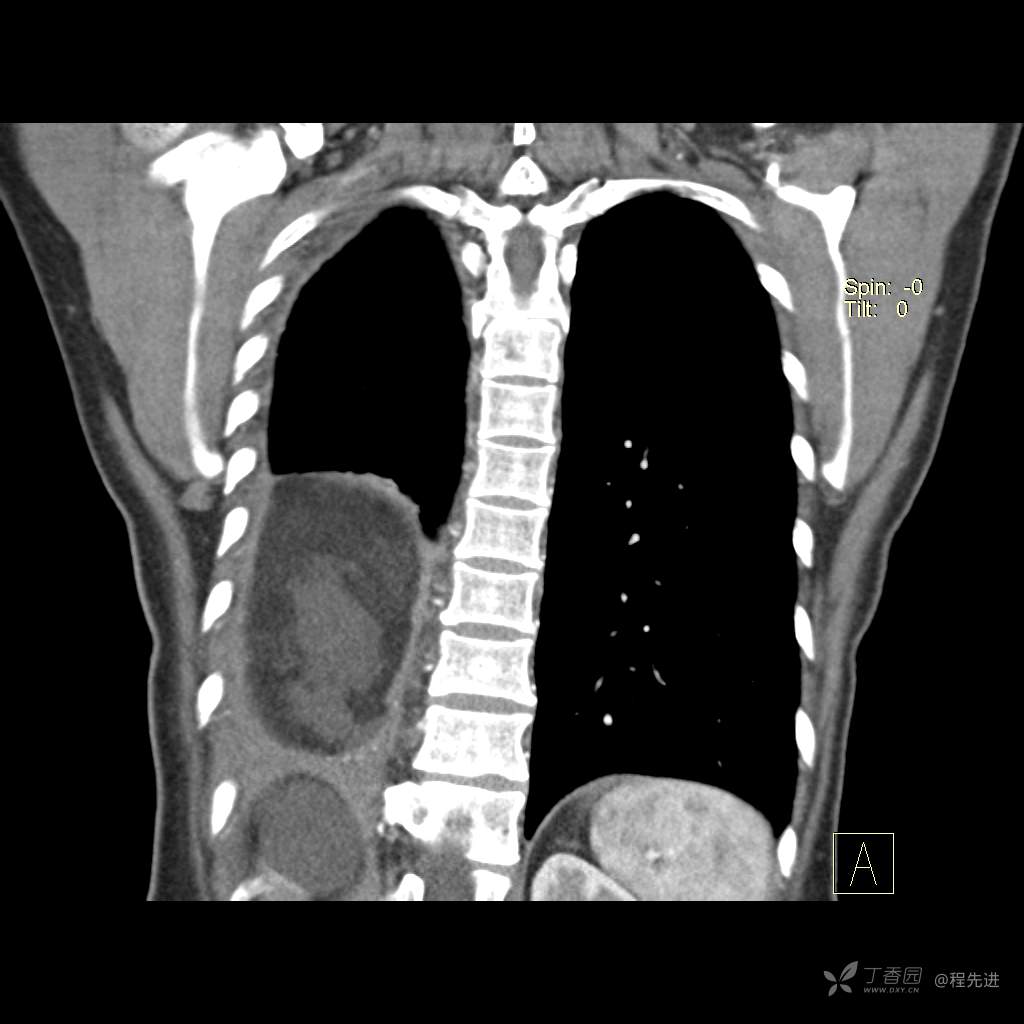

患者性别:女

患者年龄:51岁

简要病史:胸闷半年